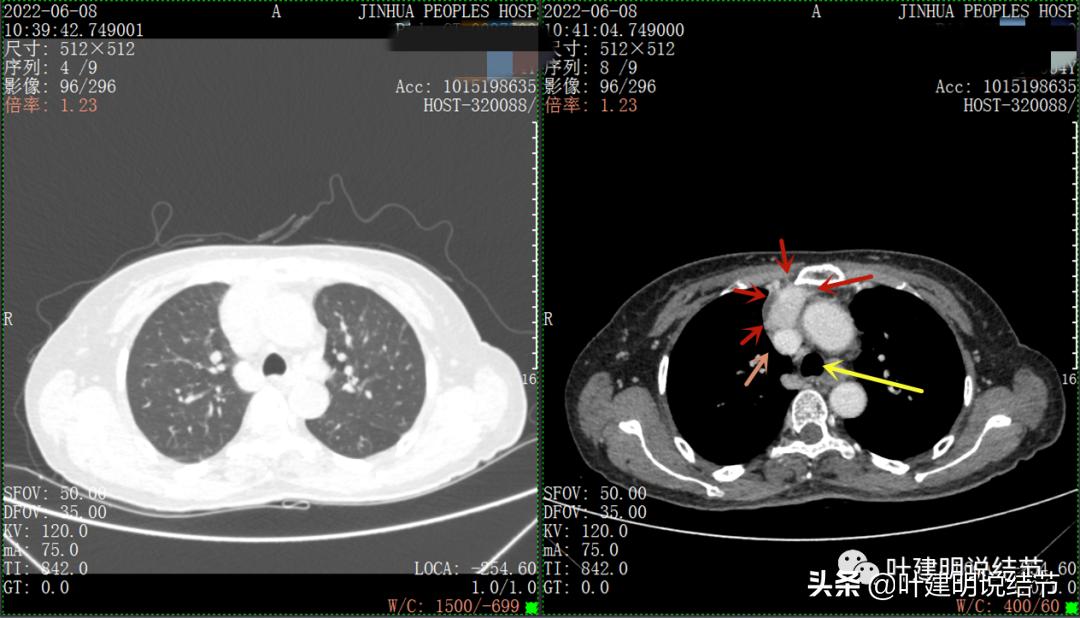

以下图片左侧是肺窗,右侧是纵隔窗。红色箭头示病灶,桔色箭头示无名静脉,黄色箭头示支气管,砖色箭头示上腔静脉,蓝色箭头示主动脉,紫色箭头示肺动脉。

病灶纵隔胸膜侧非常光滑,说明来源于纵隔

粉色箭头示淋巴结可能